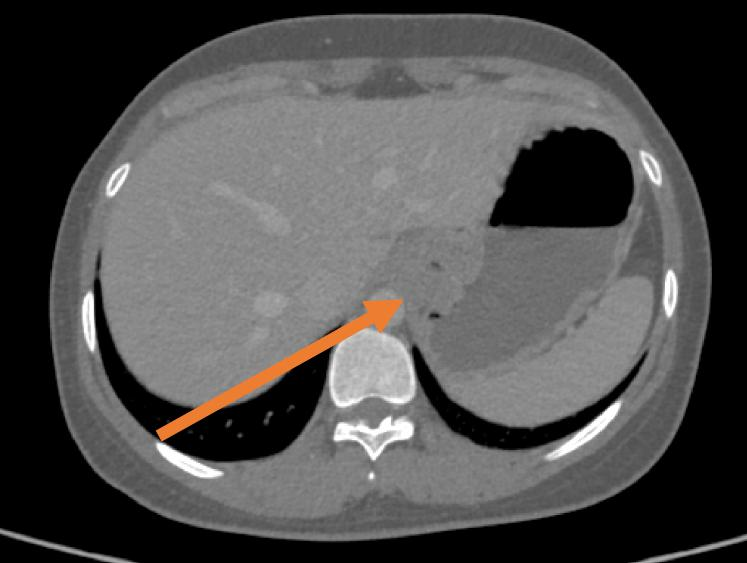

The patient, a 30-year-old female visited hospital with belching and difficulty swallowing symptoms and sought medical attention in Changzhou No.2 People’s Hospital. An enhanced chest CT scan indicated significant thickening of the lower esophageal wall near the cardia, with the thickest part measuring approximately 2.5 cm, showing mild enhancement in CT examination.

The endoscopic ultrasound showed a submucosal tumorin the lower segment of the esophagus, with a smooth surface and a ring-shaped tumor at the cardia. A hypoechoic mass is located at 37-43 cm from the incisors, with uneven internal echoes, pressing against the esophageal wall and having indistinct boundaries with the esophageal wall, measuring 5.8*3.7 cm in section.

The 3D reconstruction indicates that a large tumor encircles the esophagus and it is adjacent to the aorta. The tumor has a "hoof-shaped" around the junction of the esophagus and the cardia, with the major axis measuring approximately 6.4 cm and the minor axis measuring approximately 3.7 cm.